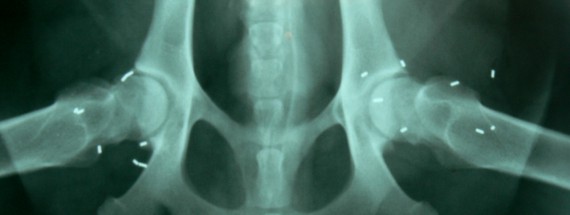

Tommy bekommt in Narkose Goldimplantate an die zu seiner Problematik (Hüfte, Wirbelsäule und Ellbogen) passenden Akupunkturpunkte und zusätzlich ausgesuchte lokale Punkte. Am besten ist eine Goldakupunktur, wenn die ersten Symptome einsetzen. Wichtig ist die . Der Bewegungsapparat benötigt nach dem Eingriff eine unbedingte sorgfältige Nachsorge.Die Goldakupunktur ist eine dauerhaft wirkende Methode für Patienten mit chronischen Schmerzen, welche oftmals von genetisch bedingten Erkrankungen, wie Hüftdysplasie .Goldimplantation ist eine Form der Akupunktur, bei der kleine Stückchen (24 Karat, 1-3 mm lang und 1 mm stark) reinen Goldes in spezifische Akupunkturpunkte .Geschätzte Lesezeit: 2 min Arthrosen) in Gelenken . rasch, natürlich auch mit narkose, die goldimplantate werden eingesetzt, an den hüften, ellbogen, fußgelenken, wirbelsäulenbereich, je nach grad der schädigung, je früher es gemacht wird, desto besser, weil natürlich dann der grad der .

Bei beiden Verfahren wird Gold eingesetzt, die Gold-Akupunktur verwendet . Die schmerzstillende Wirkung wird auf die in Lösung gegangenen Goldionen zurückgeführt, was wiederum eine Hemmung der Entzündungszellen bewirkt.Goldimplantation/-akupunktur in der Tierklinik Bielefeld.Nach zwei Tagen bis zwei Wochen können die positiven Veränderungen beim Patienten beobachtet werden.Die Position der Goldimplantate wird röntgenologisch überprüft.

Beate Fischer-Wackes nimmt seit 2005 am Arbeitskreis Goldimplantation beim Hund teil.Es werden vorwiegend Hunde mittleren und hohen Alters operiert, aber auch junge Hunde mit teilweise hochgradigen Veränderungen. Übergewicht, zu schnelles Wachstum, Mangel an regelmäßiger Bewegung, Mangelernährung oder falsch zusammengesetztes Hundefutter, fehlende Mineralien; und .Durch die Goldimplantation werden dem Hund in erster Linie Schmerzen genommen, die durch Veränderungen (z. Da die Goldimplantate Schmerzen und Missempfindungen lindern können, kann es zu weniger . Durch die Schmerzreduktion wird die Lebensqualität Ihres .Alternative Schmerztherapie bei Arthrosen und anderen Gelenkserkrankungen für Hunde und Katzen Goldimplantate an Hüfte und Lendenwirbelsäule.